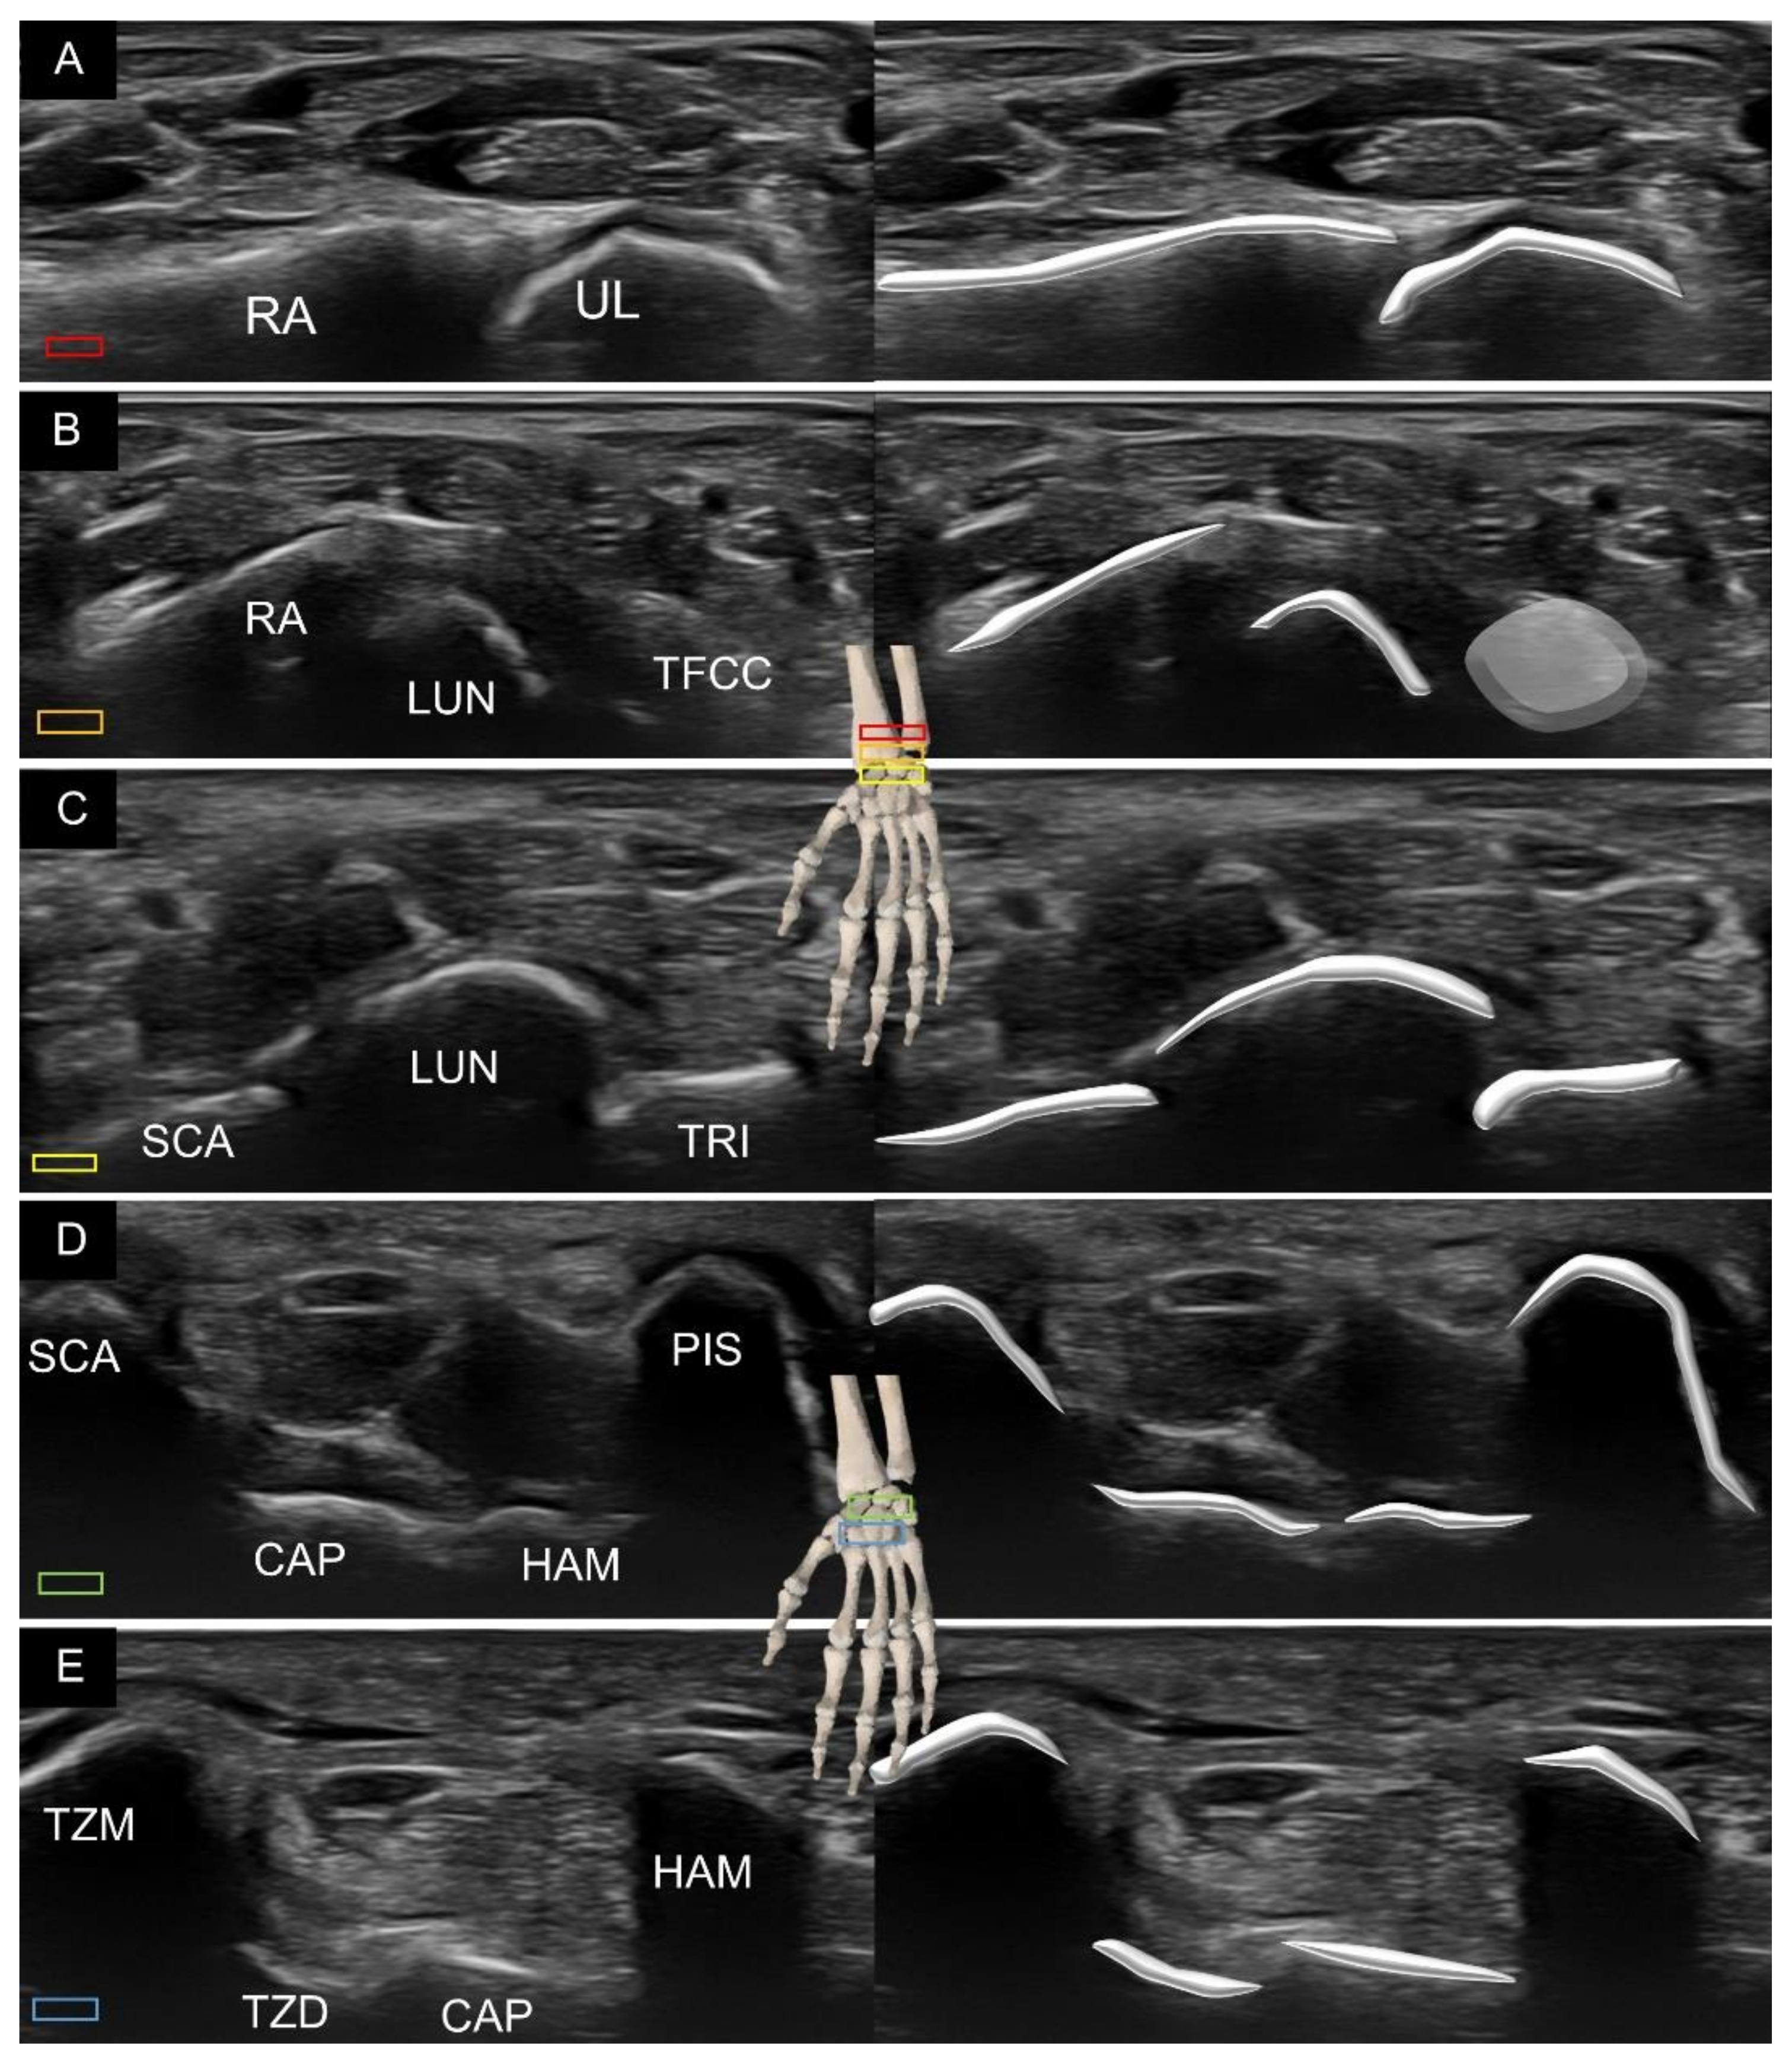

2. Sonoanatomy of Carpal Bones

3. Sonoanatomy of Volar Extrinsic Carpal Ligaments

3.1. Attachment to the Capitate

3.2. Attachment to the Lunate

3.3. Attachment to the Triquetrum